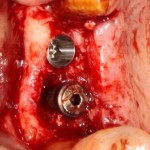

результат:

или

с трудом выковыриваем сетку и ищем имплантат:

чтобы поставить формирователь: